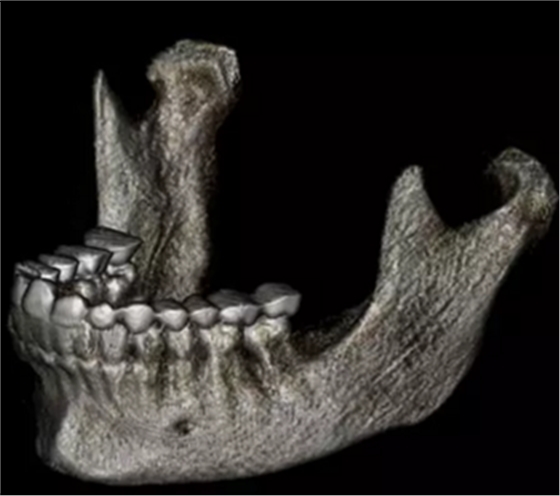

在輸出的3D模型上,使用體內(nèi)軟件(Anatomage,San Jose,Calif)將下頜骨以最小的間隔從顱骨上分離(圖5)用于保留下頜骨的咬合細(xì)節(jié),游離的下頜骨被保存(圖6,A)。同時(shí),將沒有下頜骨的顱骨導(dǎo)出并保存(圖6,B)。

圖6. A,從整個(gè)3D模型上修剪的下頜骨; B,修剪的顱骨。

使用體內(nèi)軟件,第一次融合包括咬合導(dǎo)板在下頜牙齒上定位(圖7)。 圖8顯示了咬合導(dǎo)板和下頜骨(類似咬合導(dǎo)板/游離下頜骨)的完整定位。第二次融合涉及咬合導(dǎo)板的上頜牙齒與顱骨上的的上頜牙齒的定位(圖9)。除了原始的下頜骨最小牙尖分離的3D模型(圖10)之外,這將產(chǎn)生一個(gè)構(gòu)建好的下頜骨完全咬合的3D模型。